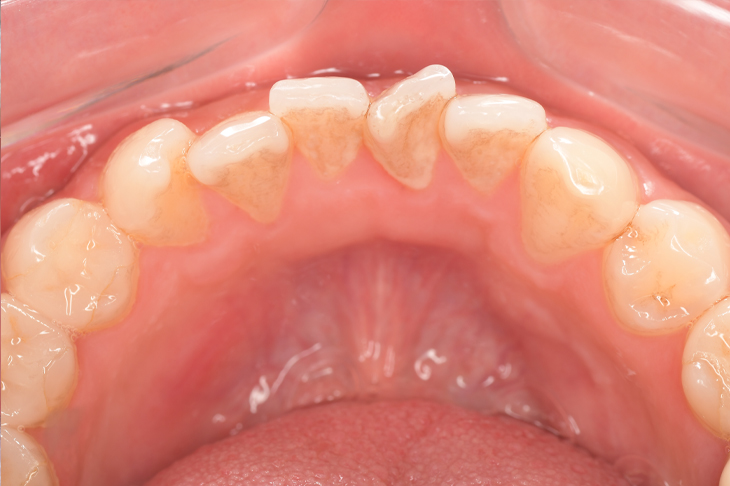

Before①

Before②

基本情報

| 年齢・性別 | 38歳・男性 |

| 主訴 | 下顎 歯石除去したい |

| 治療内容 | スケーリング |

| 治療期間 | 30分 |

| 治療費 | 約1,500円(保険診療) |

| リスク・副作用 | 知覚過敏、歯肉退縮 |

| 治療方針 | 歯肉縁上歯石を除去してから歯肉縁下歯石を除去します。ご自身でのプラークコントロールができるようになったら定期検診に移行します。 |

| 担当者所見 | 半年ぶりの歯科医院の受診。歯石が付きやすいためセルフケアの重要性をお伝えして、定期的にクリーニングを行います。出血率が高く炎症が強いため、今後はセルフケアを強化して歯周病治療を行います。 |